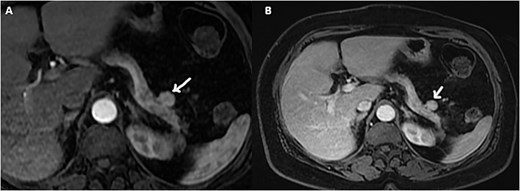

The pancreatic MRI confirmed the presence of a small, well-defined, round mass with regular contours, solid with an intermediate T2 and T1 signal, unrestricted diffusion, and appearing to be connected to the tail of the pancreas. Furthermore, the mass showed intense enhancement during the arterial phase and homogenization at portal phase (Fig. 1).

Axial gadolinium contrast T1 weighted images arterial (A) and portal phase (B) showing a small mass adjacent to the tail of the pancreas with intense arterial enhancement.